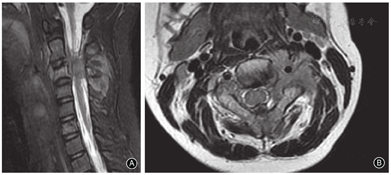

第二次手术后2周患者出现颈部疼痛、活动受限,再次入院行颈椎MR检查示C2-4椎体周围及椎间可见团块状不规则形(图5)。胸部CT扫描示双肺多发异常信号,考虑转移瘤。手术部位无局部复发现象发生。依据身体状况又给予顺铂及表柔比星方案的化疗,效果欠佳。逐渐出现、全身恶病质、呼吸不畅,于2019年7月28日死亡。

第二次手术后2周颈椎MR检查矢状面和水平面T2WI示C2-4椎体周围及椎间可见团块状不规则形

患者于做完第二次手术后两周出现颈部疼痛、活动受限,颈椎MR检查示:C2-4椎体考虑转移(图5)。胸部CT扫描结果考虑转移瘤。又给予化疗一次,效果欠佳。逐渐出现、全身恶病质、呼吸不畅,于2019年7月28日死亡。